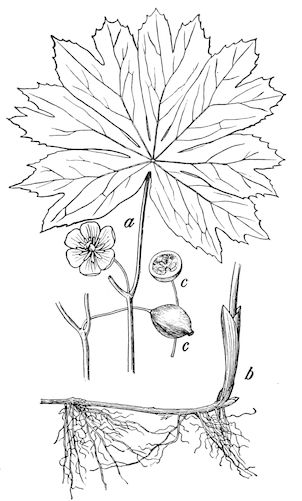

18In the final stages, the bones may be cut with a knife, and a time arrives when bony tissue seems completely to have disappeared; thus, as shown in Fig. 8 herewith, it was possible to cut the entire head of a pig into thin slices without the slightest difficulty. All parts of the head had been affected by the softening change.